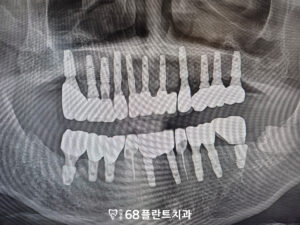

형태와 색상을 모두 자연스럽게 맞추어,

환자분과 함께 상의 후

영구접착을 진행하였습니다.

이로 인해, 자연스럽고

균형 잡힌 결과를

얻을 수 있었습니다.

◆ 전 > 후 ◆

전체적인 치료가 마무리된 후,

환자분께서는 치주질환으로 인해

안 좋았던 치아들을 발치하고

회복할 수 있어

매우 만족해주셨습니다.

또한 치료하면서

심미적인 부분까지 개선할 수 있어,

환자분은 자연스러운 미소를 되찾고

자신감을 회복하셨습니다.